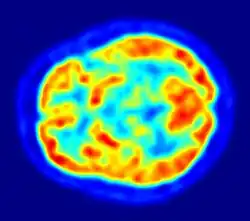

La TEP repose sur le principe général de la scintigraphie qui consiste à injecter un traceur dont on connaît le comportement et les propriétés biologiques pour obtenir une image du fonctionnement d'un organe ou la présence d'une cible moléculaire. Ce traceur est marqué par un atome radioactif (carbone, fluor, azote, oxygène, etc.) qui émet des positons dont l'annihilation produit deux photons. C'est la détection en coïncidence de ces photons qui permet la localisation de leur site d’émission et donc la concentration du traceur en chaque point de l'organe. C'est cette information quantitative que l'on représente sous la forme d'une image faisant apparaître en couleurs les zones de forte concentration du traceur.

Ainsi, la TEP permet de visualiser les activités du métabolisme des cellules : on parle d'imagerie fonctionnelle par opposition aux techniques d'imagerie dite structurelle comme celles basées sur les rayons X (radiologie ou CT-scan scanner) qui réalisent des images de l'anatomie. Par conséquent, la tomographie par émission de positons est un outil diagnostique qui permet de déceler certaines pathologies qui se traduisent par une altération de la physiologie normale comme les cancers, mais aussi les démences par exemple.

Une caméra TEP est un appareil qui a l’aspect d’un scanner mais son principe de fonctionnement est différent. En effet, l'atome radioactif (par exemple, le fluor 18) se désintègre en émettant un positon. Celui-ci va s'annihiler avec un électron du milieu, après un très court parcours de l'ordre du millimètre (0,6 mm dans l'eau pour le positon du 18F). Cette annihilation produit deux photons gamma de 511 keV qui partent sur une même direction mais dans un sens opposé, ce qui rend possible le traitement tomographique des données. En effet, les capteurs situés tout autour du patient détectent les photons d'annihilation en coïncidence (c’est-à-dire ceux qui arrivent en même temps), ce qui permet d'identifier la ligne sur laquelle se situe l'émission des photons. Un système informatique reconstitue ensuite à l'aide d'un algorithme de reconstruction les images de la répartition du traceur au niveau d’une partie ou de la totalité du corps sous la forme d'une image 2D ou d'un objet 3D. Les images ainsi obtenues sont dites « d’émission » (la radioactivité provient du traceur injecté au patient). La résolution spatiale de l'image ainsi obtenue est comprise entre 4 et 7 mm en imagerie clinique (pour l'homme) et inférieure à 1,5 mm en imagerie préclinique (destinée au rat ou à la souris)[7].

Toutes les informations recueillies par la caméra TEP reposent sur la radioactivité repérée dans les tissus après l'injection du 18F-FDG au patient. Le système informatique relié à la caméra TEP produit des images en coupe et en trois dimensions des endroits du corps où le 18F-FDG s'est accumulé.

Imagerie cérébrale TEP en neurologie

Le principe de l'utilisation de la TEP en imagerie cérébrale (neurologie et neurosciences cognitives) repose sur le lien entre activité des neurones dans une région donnée et la mesure de la radioactivité. Ce lien est indirect puisqu'au travers de la TEP, on mesure l'accumulation d'un radiotraceur. Le radiotraceur le plus couramment utilisé est le FDG qui mesure la consommation de glucose des neurones. En recherche on a aussi pu utiliser l'oxygène 15 dont l'accumulation est due à la réponse hémodynamique, c'est-à-dire une augmentation locale du débit sanguin cérébral qui se produit lorsqu'une région du cerveau voit son activité augmenter. L'imagerie cérébrale TEP reflète donc l'apport d'énergie régionale mais elle est très liée à l'activité cérébrale proprement dite.

Aujourd'hui la TEP au FDG peut-être utilisée en routine clinique pour le diagnostic des maladies cérébrales dégénératives comme la maladie d'Alzheimer. De nombreuses études récentes ont démontré l’intérêt de l’utilisation de la TEP pour un diagnostic précoce de la maladie d’Alzheimer et pour le diagnostic différentiel d'une démence ou d'un déficit cognitif léger (MCI). On observe des réductions du métabolisme glucidique au niveau de régions spécifiques selon les pathologies en cause.